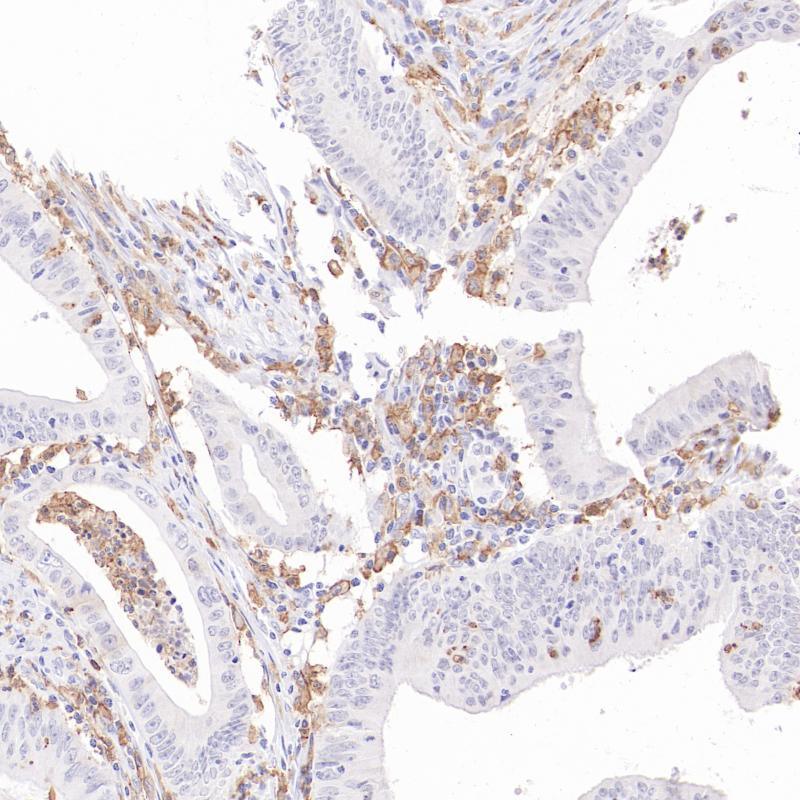

CD16 重组兔单克隆抗体

CD16,也称为Fcγ受体III (FcγRIII) ,属于免疫球蛋白超家族的糖蛋白。它有两种亚型:CD16a(FcγRIIA)和 CD16b(FcγRIIIB)。CD16a主要在自然杀伤细胞、巨噬细胞和肥大细胞上表达,而CD16b则主要存在于粒细胞中。在病理诊断中,CD16的表达有助于识别和区分NK细胞与某些T细胞亚群,这对于淋巴细胞亚群分类和其功能分析至关重要。

阳性对照

结肠癌

亚细胞定位

细胞膜